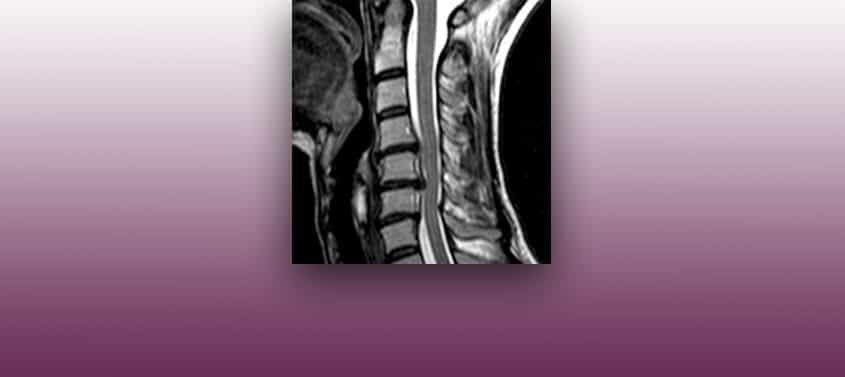

Грыжа межпозвонкового диска шейного отдела

Последнее редактирование: 02/03/2020, Доктор Мигель Б. Ройо Сальвадор, Номер в коллегии: 10389. Нейрохирурга и Невролога. Диагностика Грыжа или протрузия межпозвоночного диска на уровне шейного отдела может задеть нервные корешки или спинной мозг. В этом отделе позвоночника очень мало свободного пространства для дисков, отсюда более частое возникновение грыж с компрессией нервных корешков или спинного […]